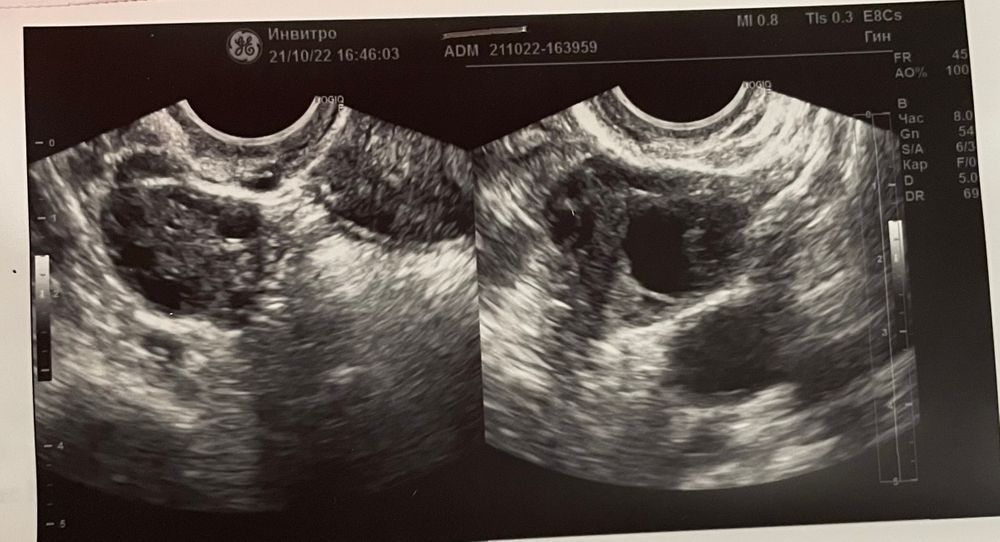

В этом цикле была оф.гистера,всё ок, разрешили пробовать. На 19ДЦ сказали это ЖТ 20*19 похоже? Жидкость менее 1мл. Если да, сегодня третий день задержки. Возможно из-за перелёта задержка? Обычно отслеживаю овуляцию и вторая фаза стабильная. Делала 2 дня назад тест было пусто